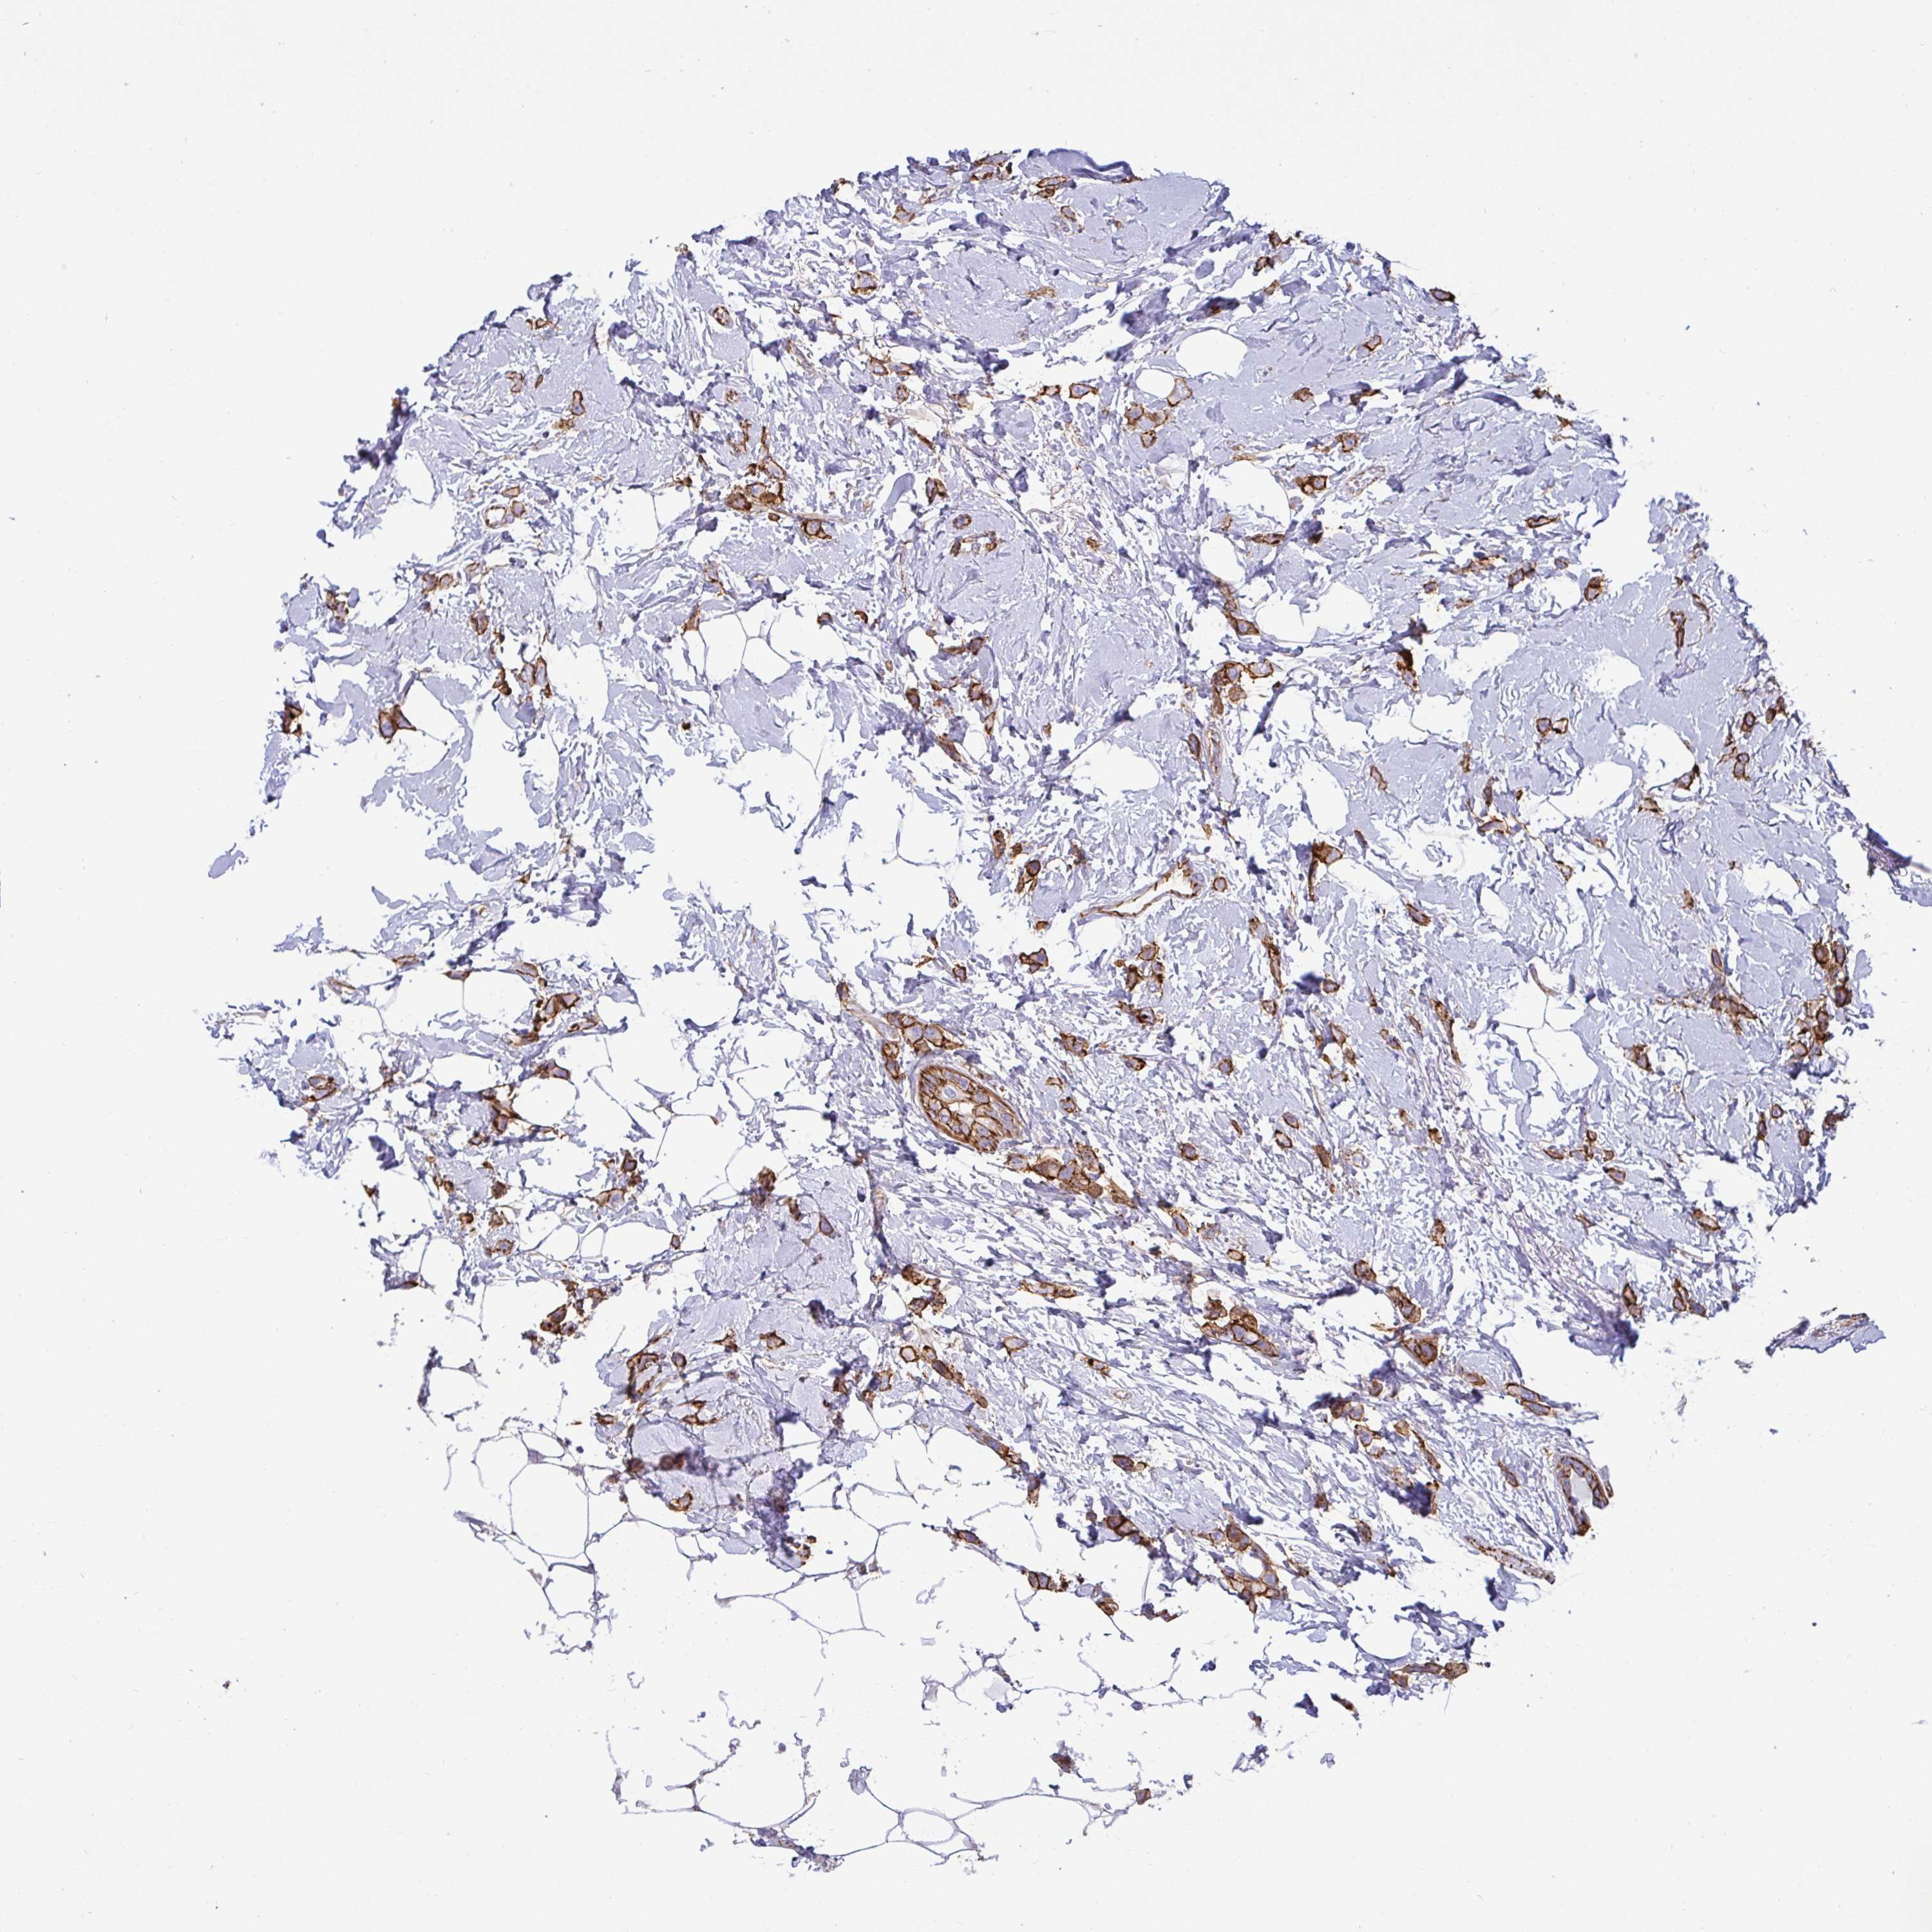

CANCER BREAST CANCER Show tissue menu

BRCA TCGA BRCA VALIDATION PROTEIN EXPRESSION